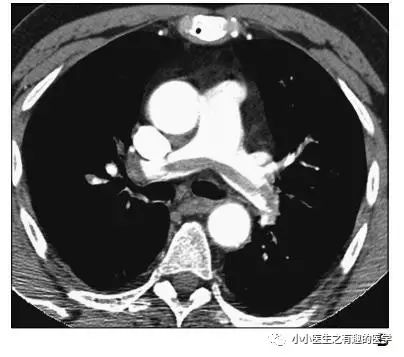

再来一个

很明显:扯蛋肺栓塞。

没看够?

再来一个,让你一次看个够。

不光是肺栓塞,连主动脉夹层,都发现了。

牛。我来标记一下。